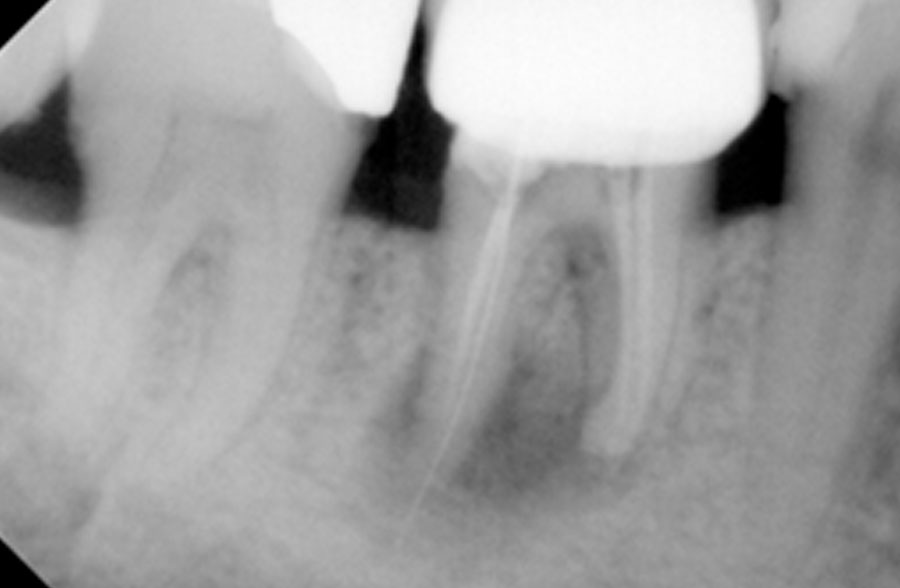

Χρόνια φλεγμονώδης περιακρορριζική βλάβη, κυρίως,

λόγω ενδοδοντικής αιτιολογίας. Μετά την ενδοδοντική θεραπεία

ακολούθησε περιοδοντική θεραπεία.

Δύο χρόνια μετά, παρατηρείται πλήρης εξαφάνιση της βλάβης.